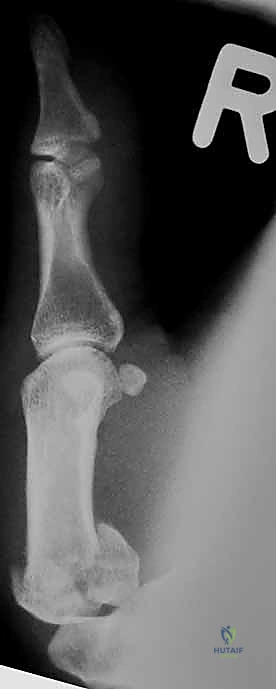

* المنظور الجانبي الحقيقي (True Lateral View): وهو ضروري جداً لتقييم مدى الخلع أو الانزياح في المفصل.

* منظور روبرت (Robert's View): وضعية خاصة للأشعة السينية تظهر مفصل الإبهام الرسغي السنعي بوضوح تام وتكشف عن أدق التفاصيل في كسور بينيت ورولاندو.